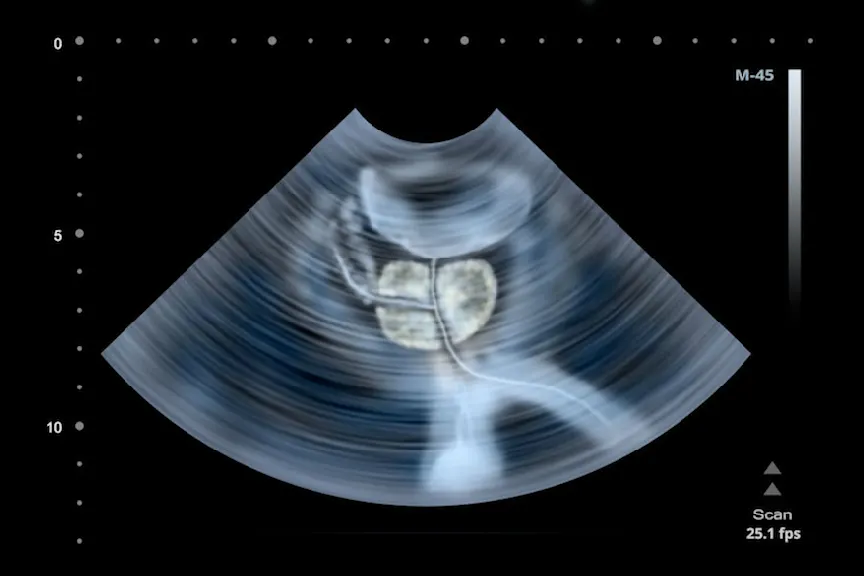

今天,前列腺癌在晚期的诊断是不寻常的,因为对这种疾病的广泛筛查前列腺特异性抗原(PSA)血检。

了解更多关于前列腺癌肿瘤如何分期和如何找到前列腺肿瘤医生。